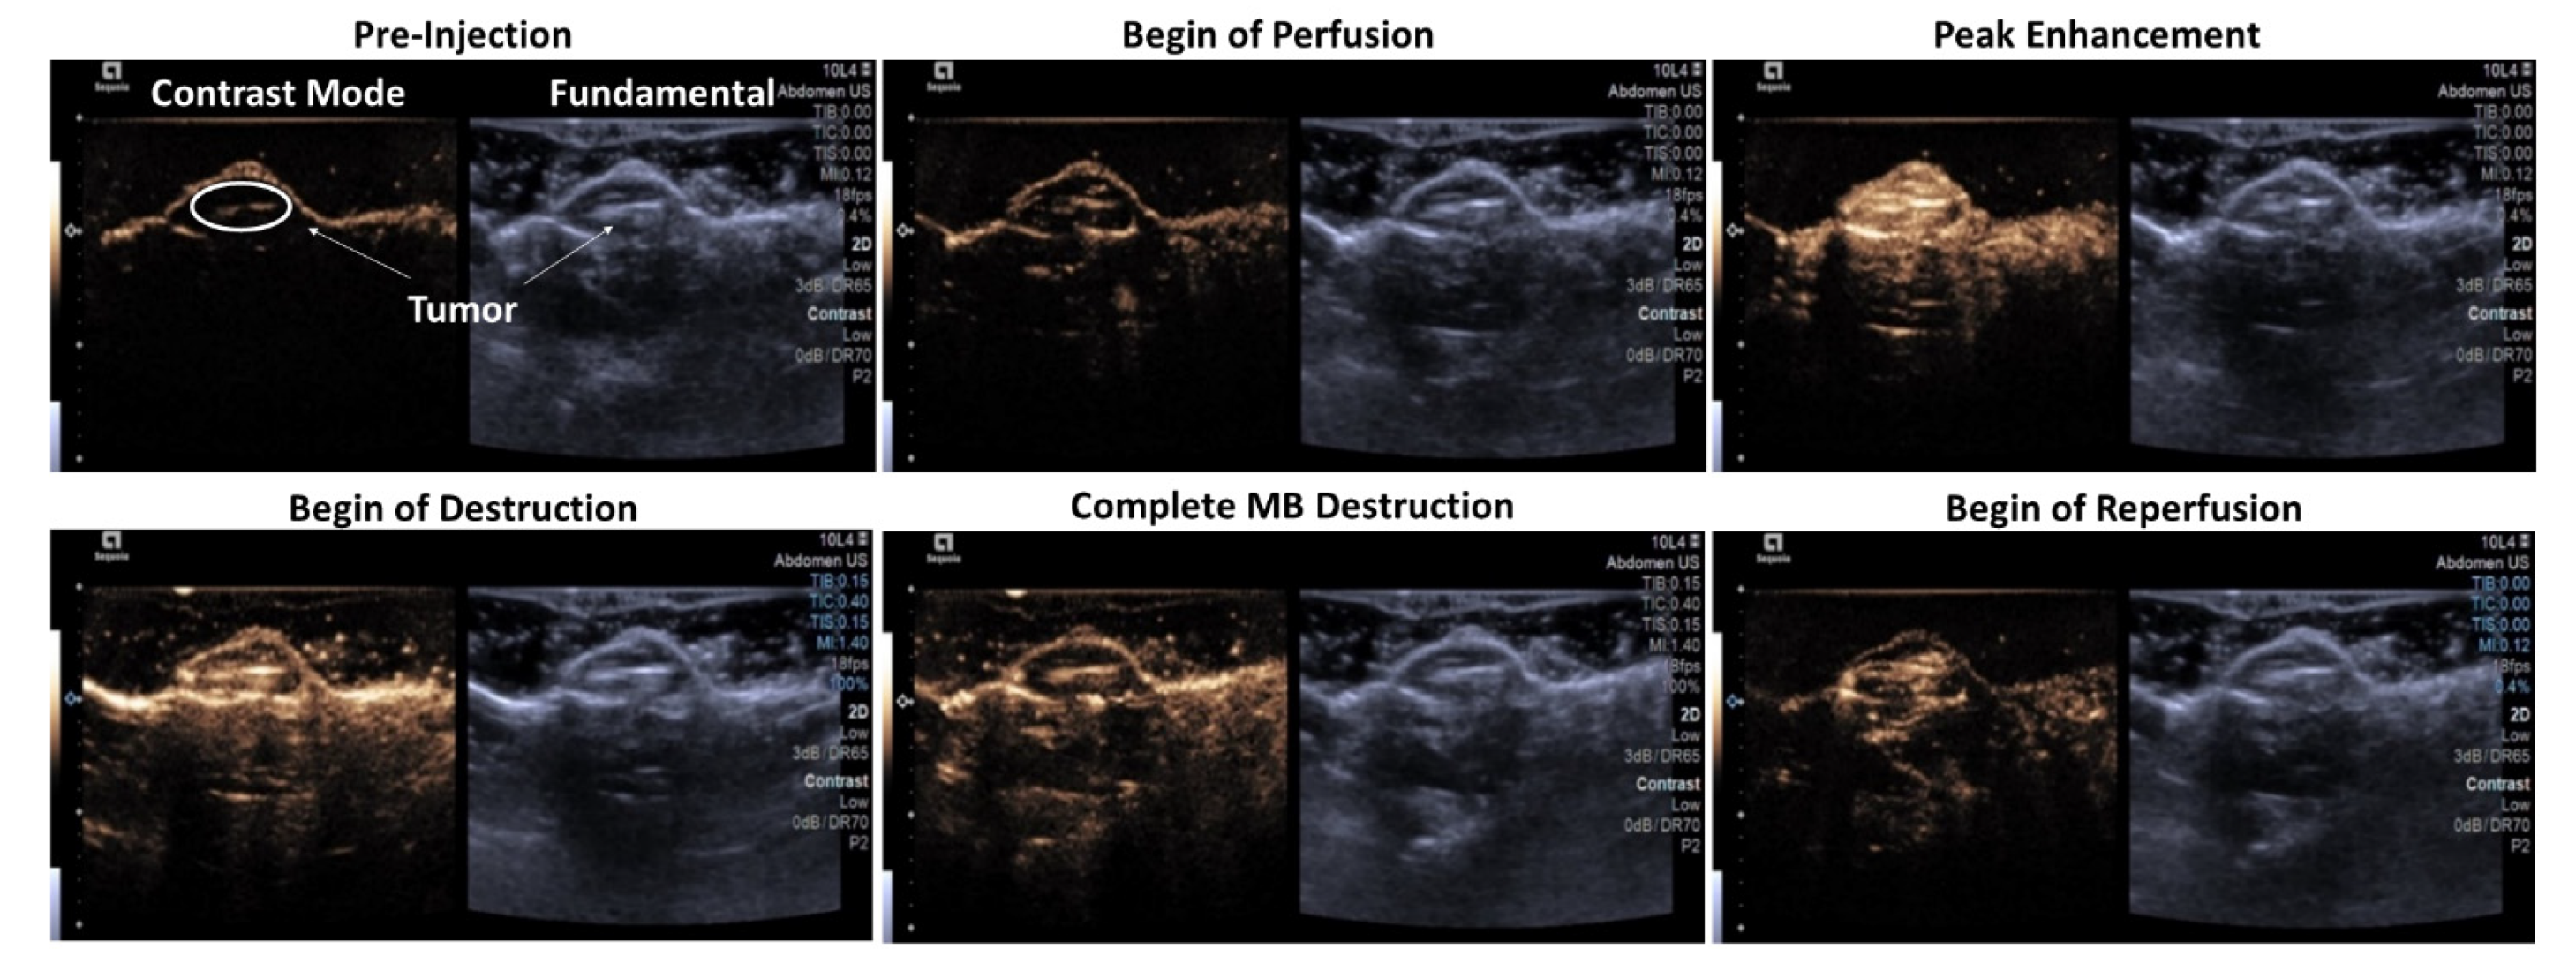

3.2. Microbubble Imaging In Vitro and In Vivo